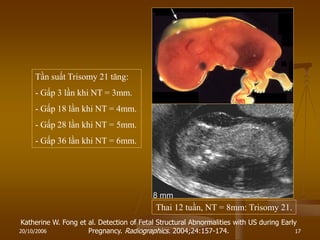

Thai 12 tuần, NT = 8mm: Trisomy 21.

Katherine W. Fong et al. Detection of Fetal Structural Abnormalities with US during Early

Pregnancy. Radiographics. 2004;24:157-174.

Tần suất Trisomy 21 tăng:

- Gấp 3 lần khi NT = 3mm.

- Gấp 18 lần khi NT = 4mm.

- Gấp 28 lần khi NT = 5mm.

- Gấp 36 lần khi NT = 6mm.